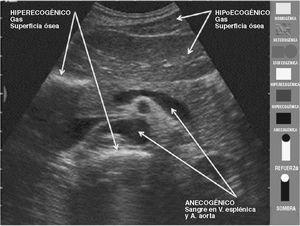

INCONVENIENTES/LÍMITES DE LA ECOGRAFÍA

Gas y superficie ósea

Ninguna de estas estructuras permiten observar lo que hay detrás mediante ecografía. Para salvar estos inconvenientes es preciso conocer y emplear "ventanas acústicas": vías de acceso y maniobras para que los ultrasonidos alcancen la zona que se quiere estudiar. Por ejemplo, el contenido líquido de la vejiga hace de ventana para valorar la pelvis7.